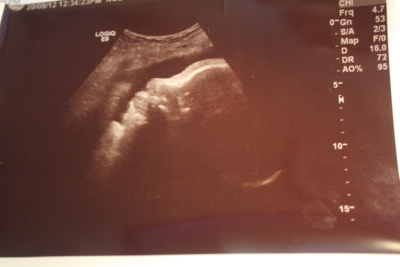

Here is an ultrasound picture of my baby at 37 weeks. the picture isnt that great but any guesses would be welcomed.